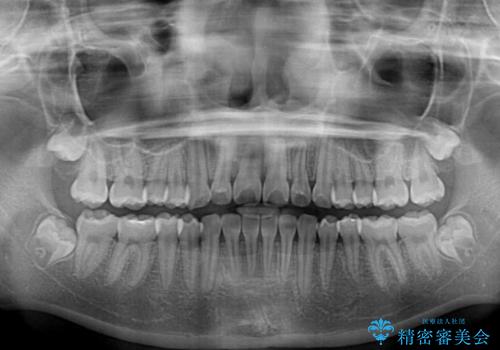

- クリアブラケット

- 11ヶ月

- 10-30回